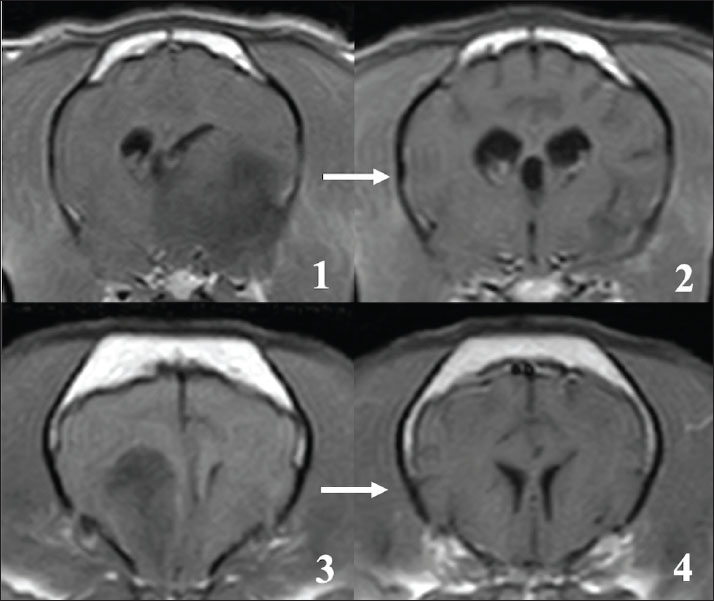

Radiotherapy improved the clinical symptoms of all patients who completed treatment, completing the radiotherapy schedule. In 7 cases with persistent seizure, antiepileptic medication was continued during and after radiotherapy. However, locomotor dysfunctions, such as ataxia and compulsive walking, improved in all 11 cases. MRI examinations performed after the final dose showed regression of primary tumor tissues in all cases (Fig. 2). In 7 cases, tumor tissue completely disappeared on MRI, and in the other 4 cases, showed apparent reductions and in tumor size as measured on MRI images. In all cases, CT evaluations of the thoracic and abdominal cavities performed with the last dose of the radiotherapy showed no distant metastatic lesions. At the end of radiotherapy, all patients were in an acceptable physical condition.

Fig. 2. The effect of radiotherapy on primary brain tumors in FBs. 1, 3: MRI findings before irradiation (contrast-enhanced T1-weighted image). 2, 4: MRI findings immediately after the final fraction of radiotherapy (contrast-enhanced T1-weighted image). Tumor tissue almost disappeared on MRI after radiotherapy.